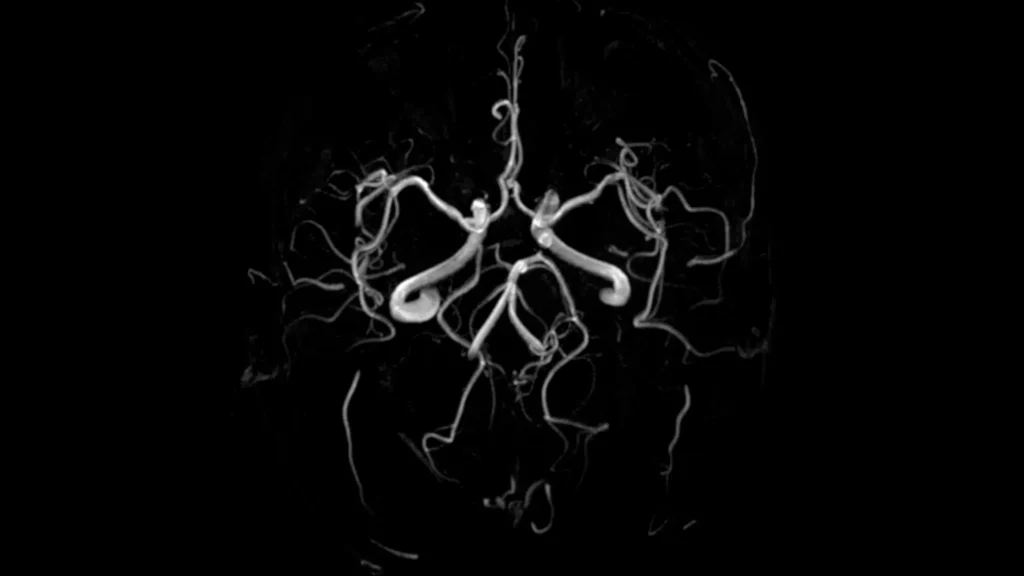

CT SCAN

img01

CT-Scan Aquilion Prime SP

• Comfortable & Fast Experience

Wide 78 cm open design and extremely fast scanning reduce stress, breath-holding, and discomfort — perfect for children, elderly, and nervous patients.

• Low Radiation for Your Safety

Advanced dose-reduction technology keeps radiation as low as possible while still delivering clear, reliable images.

• Clear & Accurate Results

High-resolution, 160-slice imaging provides sharp detail for chest, abdomen, brain, spine, blood vessels all angiographic studies (Coronary Angio) CALCIUM SCORE, full-body assessments and stroke evaluation.

• Ideal for All Patients

Comfortable for larger or mobility-impaired patients thanks to the wide opening and quick exam times.

• Great for Emergency & Routine Scans

Captures fast, precise images for trauma.

• Smooth, Quick Visit

High-speed imaging means less time on the table and faster results for your doctor.

• Vitrea post processing AI software

Multi-planer reformatting (MPR), 3D and 4D Advanced visualization, Quantitative analysis and measurement tools (Calcium score), Reduce noise and artifact.